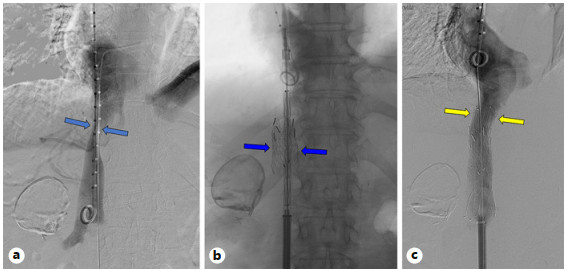

Abstract: Small bowel-origin carcinoid tumor is indolent but may metastasize relentlessly to various sites, including the liver. Over the past 9 years, we have treated a 69-year-old woman who has undergone 5 percutaneous liver ablations, 5 hepatic intra-arterial chemoembolizations, an ovarian cryoablation, and a trans-ventral hernia mesenteric cryoablation. These interventions are all related to her inoperable carcinoid malignancy. After the patient presented with swelling of the abdomen and both lower extremities, computed tomography (CT) angiography was performed, revealing a circumferential hepatic metastatic mass encasing the intrahepatic inferior vena cava (IVC) and extensive third spacing of fluids specific to the IVC distribution below the diaphragm. A venogram of the intrahepatic IVC revealed extrinsic compression causing 95% narrowing of the vessel. A balloon was advanced to the level of the lesion and inflated, increasing the caliber of the vessel. Subsequently, 2 covered aortic stent graft cuffs were deployed in an overlapping fashion within the lumen of the IVC, traversing the area of narrowing. Next, an open-cell aortic dissection stent was placed across both overlapping aortic stents from the renal veins to the hepatic veins. Following this, three 17-gauge cryoablation probes were inserted into the segment 1 intrahepatic lesions encasing the newly stented IVC via an anterior percutaneous approach. Two 10-min freeze cycles were performed with intraoperative CT imaging, demonstrating circumferential coverage of the lesions. Posttreatment venogram revealed patent stent grafts within the intrahepatic IVC, and restoration of vessel patency. No immediate postoperative complications were noted. The patient’s abdominal and lower extremity swelling resolved completely within 1 week after procedure. Two-month follow-up CT demonstrated markedly decreased size of the metastatic lesions and no adverse effects. Six- and 9-month PET-CT scans demonstrated maintained patency of the IVC stent. This palliative procedure allowed the patient to maintain good performance status and alleviated her symptoms of IVC syndrome. The radial force generated by the multiple aortic stents will ostensibly maintain the patency of the intrahepatic IVC. Cryoablation of the encasing metastatic lesion was performed with markedly decreased size of the tumor on the 2-month follow-up.